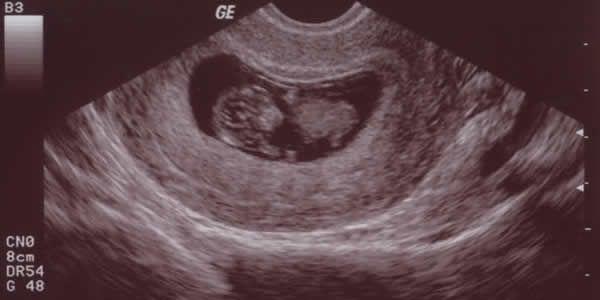

胎囊是怀孕最开始的形状,是初始的胚胎机构被羊膜、毛细血管网包囊的小胚胎。那时胎宝宝都还没产生,胎芽胎心出現时早已有胎儿心跳颤动了。

一开始胎囊是很细微的,随后再渐渐地长大了。有很多人说胎囊能看胎宝宝的性别,那麼怀孕多长时间B超能看得出胎囊呢?一般状况下,怀孕5周之后,B超可看到小孕囊,孕囊约占宫腔内不上1/4,或由此可见胎芽胎心。如果是一切正常的宫腔内妊娠,怀孕40天上下能够根据B超在子宫内见到胎囊,但是因个别差异而受孕時间的早中晚,有的孕妈妈会延迟至45天上下时才可以见到。

孕囊看男女的含意便是,能够依据b超数据单中胎囊的数据信息来剖析胎宝宝的性别。